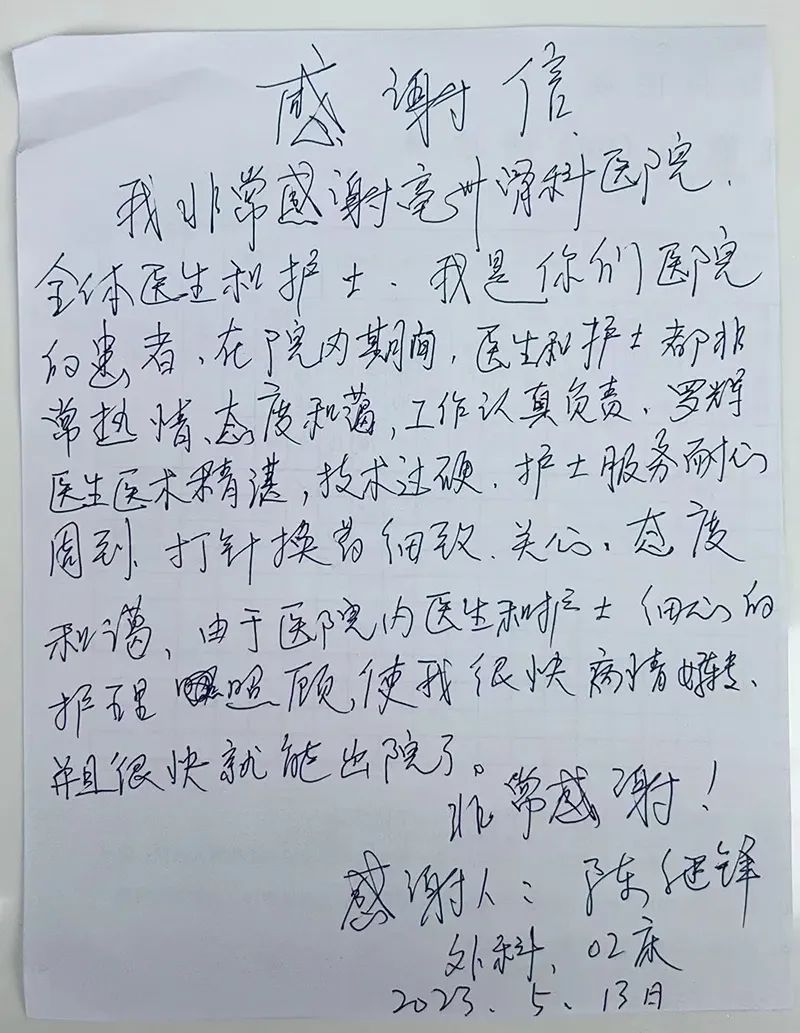

陈老板出院时说,肾结石不大,但是痛苦不小,以前只听说过微创手术,没想到真的是微创,很快就解决了他的问题。感谢住院期间护士全程带着他做术前检查,还安慰他,告诉他不要紧张,手术不开刀,使用内镜钬激光治疗,无创手术,增加了他的信心。医生技术好,手术时间很短,术后恢复很快,非常感谢亳州骨科医院外科全体医生和护士。

亳州骨科医院外科成立于2019年,是亳州骨科医院重点科室。本科设有专家门诊、普通门诊、外科急诊,治疗室(换药室、清创室、门诊手术室)。聘请亳州外科专家于坦然主任医师、王进先主治医师等长期坐诊,建院来外科门诊接诊9000余人次、住院诊治2000余人次、完成手术1600余人次、科室获得荣誉10余项、个人荣誉30余项、收获锦旗200余面、感谢信300封、外出进修3人次。专家导师带领着一批青年医生本着医者仁心,悬壶济世的理念切实做到不忘初心,坚持使命,让老百姓看得起病,看得好病。